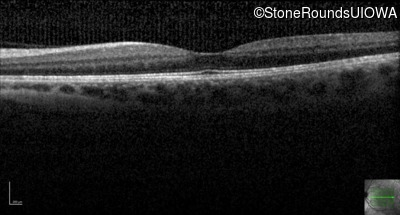

This 44 year old woman has had very poor vision in dim light for her entire life. She vividly remembers running into a picnic table on a bicycle in a campground as a child.